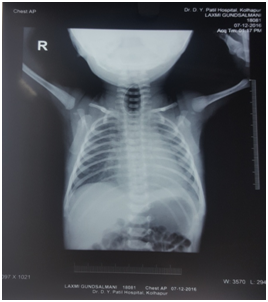

An 1 day old neonate of 36 week gestational age and 2700 gm weight was delivered at DY Patil Hospital, Kolhapur. After birth, baby had excessive frothing with respiratory distress so he was admitted to NICU with the clinical findings of heart rate 146/min, RR 50/min with intercostal / subcostal in drawing and SpO2 on air was 99%. Patient was managed with oxygen, nebulization, antibiotics. X-ray chest and abdomen showed rolling up of nasogastric tube (NGT) in upper part of esophagus and large gas shadow of stomach (Figure 1). The ECG and ECHO were normal. Routine blood investigations and ABG were within normal limits. Patient was diagnosed as a case of tracheoesophageal fistula type IIIB. High risk consent taken after the parents were informed about the risk involved and about the need of postoperative intensive care. PCV was arranged.

Figure 1 Preoperative X-ray chest of baby.